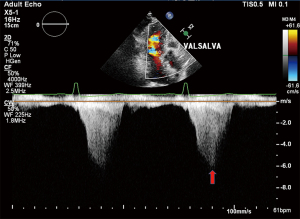

Twelve-lead electrocardiogram showed ST-T segment depression and signs of left ventricular hypertrophy. Transthoracic echocardiography (TTE) showed asymmetric septal hypertrophy with a maximal wall thickness of 16 mm at the LVOT level. Transesophageal echocardiography (TEE) revealed significant SAM of the anterior mitral leaflet (Figure 1, Video 1), causing dynamic LVOT obstruction (Figures 2,3) and severe MR (Figure 2, Video 2). On Valsalva maneuver, the LVOT pressure gradient reached 233 mmHg. Her left atrium was dilated and pulmonary artery systolic pressure was elevated. Reversed systolic wave was observed in the pulmonary vein flow (Figure 4). No abnormal muscle bundles were observed on imaging, including TEE and TTE.

Following implantation, TEE revealed significant improvement with only mild residual MR. The residual mitral valve orifice area was 1.6 cm2, and the mean diastolic trans-mitral pressure gradient increased to 4 mmHg. The LVOT gradient decreased to 81 mmHg. Invasive hemodynamic monitoring showed left atrial pressure dropped significantly from 55 mmHg pre-procedure to 25 mmHg post-procedure. Pulmonary vein flow spectrum normalized (Figure 5).